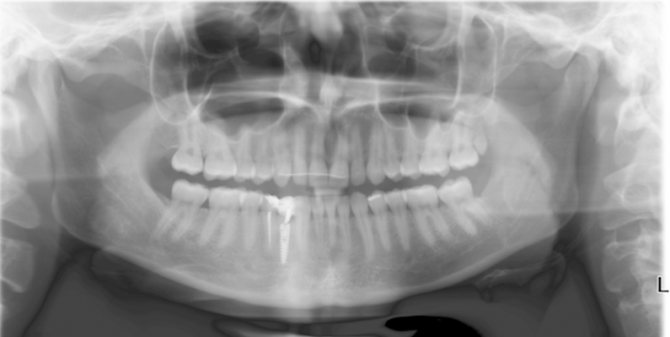

Панорамная рентгенограмма

О состоянии ротовой полости позволяют судить панорамный снимок и компьютерная томография.

Панорамная рентгенограмма показывает состояние височно–нижнечелюстного сустава, гайморовых пазух необходима при планировании операций, имплантации.

Врачи ее назначают пациентам при первичном обращении, чтобы оценить состояние верхней и нижней челюсти. Каждый человек хотя бы раз в жизни должен сделать панорамный рентген.

Также стоматологи его рекомендуют:

- перед имплантацией для оценки костных тканей, ширины и высоты нижней челюсти, расстояния до нерва и гайморовых пазух;

- перед протезированием для построения этапов лечения;

- установкой брекетов,чтобы исправить прикус;

- при удалении зубов мудрости.

Панорамная рентгенограмма помогает в ситуациях, когда трудно определить причину боли, особенно при скрытых полостях, больших пломбах и коронках. При разлитой боли пациент может ошибочно указывать на соседний здоровый зуб.

К недостаткам метода относится неодинаковая степень увеличения изображения, а также деформация анатомических структур. В этом случае лучше сделать томографию.